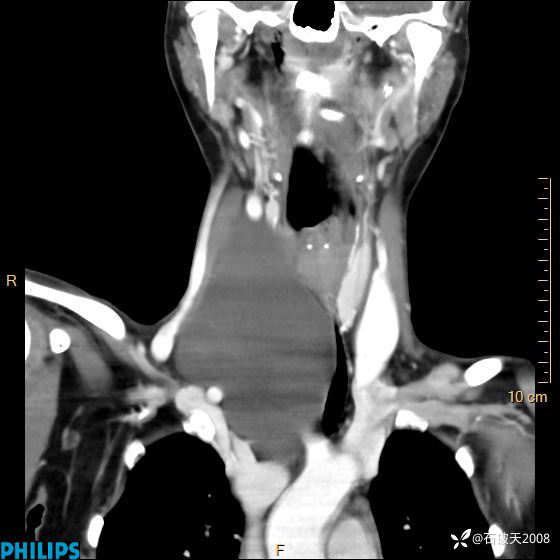

动脉期

冠状位